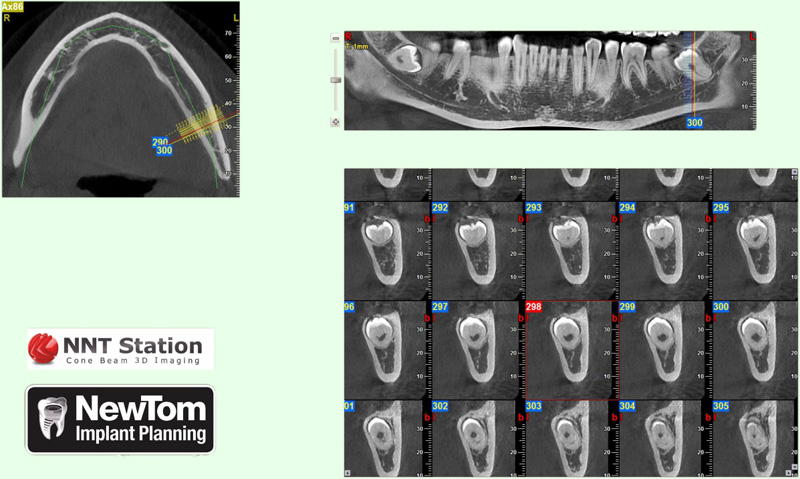

NewTom Implant Planing

Jedná se o plánovací program, který využívá dat získaných při vyšetření pomocí přístroje New Tom. Tento program umožňuje tříprostorovou počítačovou simulaci při plánování pozic implantátů.

Součástí programu je i databáze, ve které mohou být uloženy všechny typy implantátů od všech výrobců, včetně jejich délek, průměrů i tvarů.

Lékař si vytvoří všechny typy zobrazení potřebných pro naplánování – tedy 2D snímky (panoramatický), příčné řezy i 3D model.

Vidí zde i důležité anatomické útvary – čelistní dutinu, průběh nervu atd. Po proměření množství kosti – šířky i výšky vybere z databáze vhodný typ implantátu a umístí ho do požadované lokality.

Ihned vidí jeho pozici ve všech 3 rovinách a na všech snímcích i 3D modelu. Může upravovat podle potřeby jeho pozici, sklon atd.

Všechny vybrané a správně umístěné simulované implantáty se ukládají do „počítačové karty“ pacienta s jejich pozicí, délkou, průměrem, typem i sklonem.

Lékař i pacient tedy ještě před vlastní operací vidí, jak by mělo ošetření probíhat a vypadat.